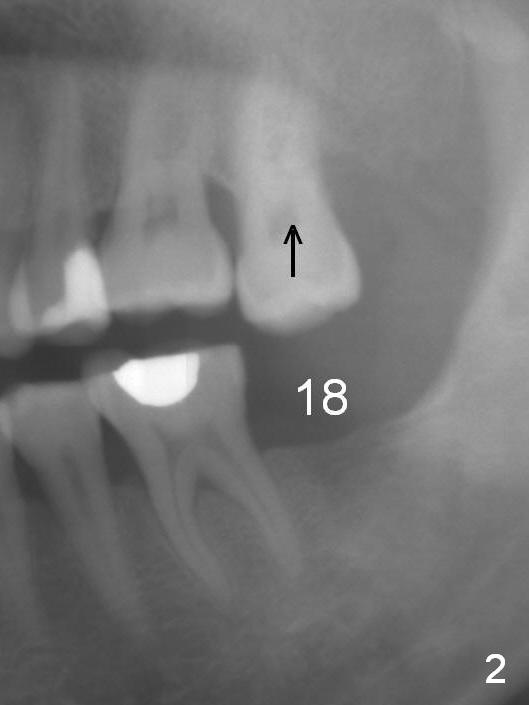

A 50-year-old man has lost the tooth #18 for 10 years; the opposing tooth (#15) has been supraerupted in the last 6 years (Fig.1,2). Mini-implants are placed to intrude the tooth #15 (Fig.2 arrow), instead leading to distalization in 4 months (Fig.3 arrow). Segmental orthodontic appliances are placed with noncompliance. Five months post implant placement at #18, a provisional (Fig.5 P) is fabricated with intentional supraocclusion. In 4 months, the marginal ridges of the teeth #14 and 15 are at the same level (Fig.4). To prevent the 2nd molar from distalization, keep the third molar if present.